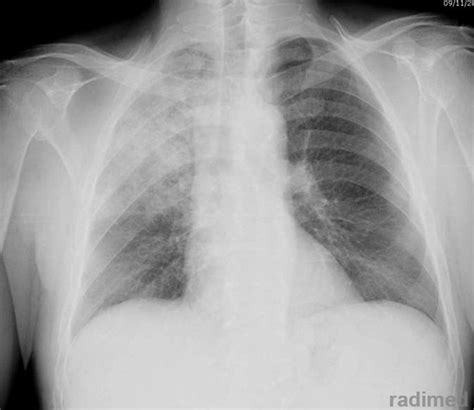

Un aspetto meno esplorato, ma potenzialmente rilevante, emerge da un referto di PET total body che evidenzia "un'area di ipercaptazione del tracciante riferibile a malattia ad elevato metabolismo glucidico a livello di un addensamento parenchimale nelle porzioni basali del polmone sinistro". Questo significa che in una specifica area del polmone si osserva un'attività cellulare notevolmente aumentata, indicativa di un elevato consumo di glucosio.

Sebbene il referto sia stato emesso in assenza di notizie cliniche specifiche sul paziente, questa scoperta apre a diverse ipotesi diagnostiche. Tra queste, la polmonite organizzata, la tubercolosi, le micosi o un tumore polmonare sono tra le possibilità da considerare. Altre patologie polmonari, come la sarcoidosi, l'artrite reumatoide, l'amiloidosi o la fibrosi polmonare, possono determinare lesioni con un elevato metabolismo, sebbene di solito si presentino come lesioni multiple anziché un singolo addensamento.

La connessione tra un'area polmonare ad elevato metabolismo glucidico e la vitiligine non è immediatamente evidente e richiede ulteriori indagini. Tuttavia, considerando la natura sistemica e autoimmune della vitiligine, è plausibile ipotizzare che processi infiammatori o patologici che coinvolgono un aumento del metabolismo cellulare in altre parti del corpo possano in qualche modo influenzare o essere correlati allo sviluppo o all'attività della vitiligine.